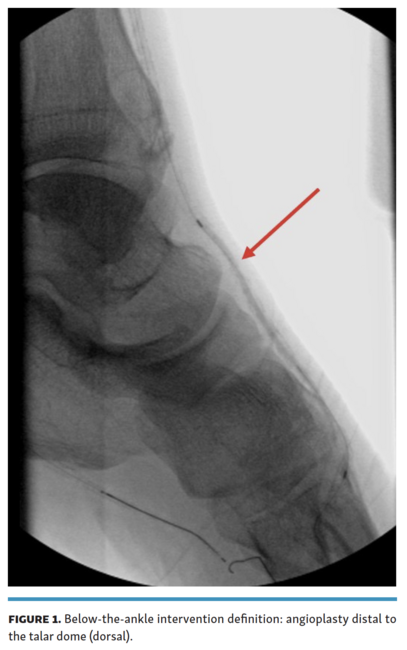

This study included patients with CLTI presenting with infrapopliteal arterial disease who underwent revascularization at a single-center office-based practice. All treated patients presented with rest pain, gangrene, and/or lower-extremity ulcerations for at least 2 weeks that were not amenable to routine medical therapy. A total of 599 consecutive lower-extremity angiograms on 381 patients were retrospectively reviewed for BTA interventions from July 2016 to December 2018. All 599 angiograms were independently reviewed by 2 interventional radiologists for BTA interventions. Exams lacking unanimous agreement were excluded from the cohort. BTA interventions were defined as angioplasty distal to the talar dome (dorsal) (Figure 1) or below the mid calcaneus (plantar) (Figure 2) on lateral digital subtraction angiography.